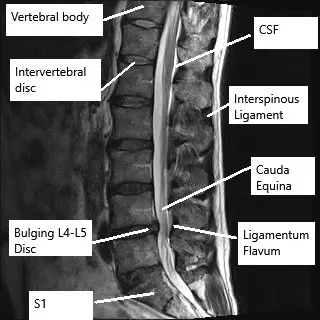

Microdiscectomy is a minimally invasive surgical procedure to help relieve the pressure from pinched nerves known as sciatica or lumbar radiculopathy. Sciatica is most commonly caused by a prolapsed intervertebral disc. During surgery, the spine surgeon removes the protruding intervertebral disc material. The recovery after microdiscectomy surgery is usually faster as compared to open discectomies and lumbar fusion surgeries.

During the surgery, a small incision measuring only a few centimeters is given on the back of the patient. The surgeon then carefully retracts the skin and the muscles in the lower back. An endoscope/microscope is used to aid the surgeon to see through the narrow incision.

A part of the vertebra known as the lamina may be partially cut to expose the intervertebral disc. The surgeon carefully retracts the spinal nerve roots and uses a special instrument to take small bites of the intervertebral disc. The protruding part of the intervertebral disc is removed and the surgeon carefully closes the incision in layers.